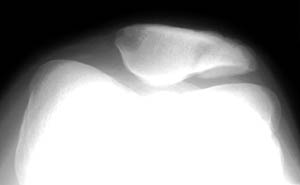

Oblique view |

Sunrise view | |

Fractures of the patella can be confused with bipartite or multipartite patella. The radiographs below

show bipartite patella. Compare the images below with those shown above. Notice that the fractured

patella has pieces that fit together like a jigsaw puzzle. The bipartite or multipartite patella has

pieces with more rounded margins that do not fit together. | ||